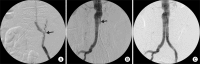

For high-risk patients, endovascular aortic aneurysm repair (EVAR) is a good option but may lead to serious complications, which should be addressed immediately. A 75-year-old man with a history of abdominal surgery underwent EVAR for an aneurysm of the abdominal aorta and iliac arteries. During EVAR, iliac artery rupture and graft limb occlusion occurred, and they were successfully managed by the additional deployment of an iliac stent graft and balloon thrombectomy, respectively. We, herein, report a rare case of the simultaneous development of the two fatal complications treated by the endovascular technique.